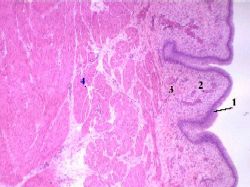

| 4,а-в. Препарат - мочевой пузырь. Окраска гематоксилин-эозином. | ||

| Слои стенки мочевого пузыря | В стенке мочевого пузыря мы встречаем те же слои, что и в стенке мочеточника: слизистую оболочку и в ней - переходный эпителий (1) и - собственную пластинку (2), | а) Малое увеличение Полный размер |

нечётко отделённую от последней подслизистую основу (3), мышечную (4) и наружную оболочки. (Последняя в поле зрения не попала). |